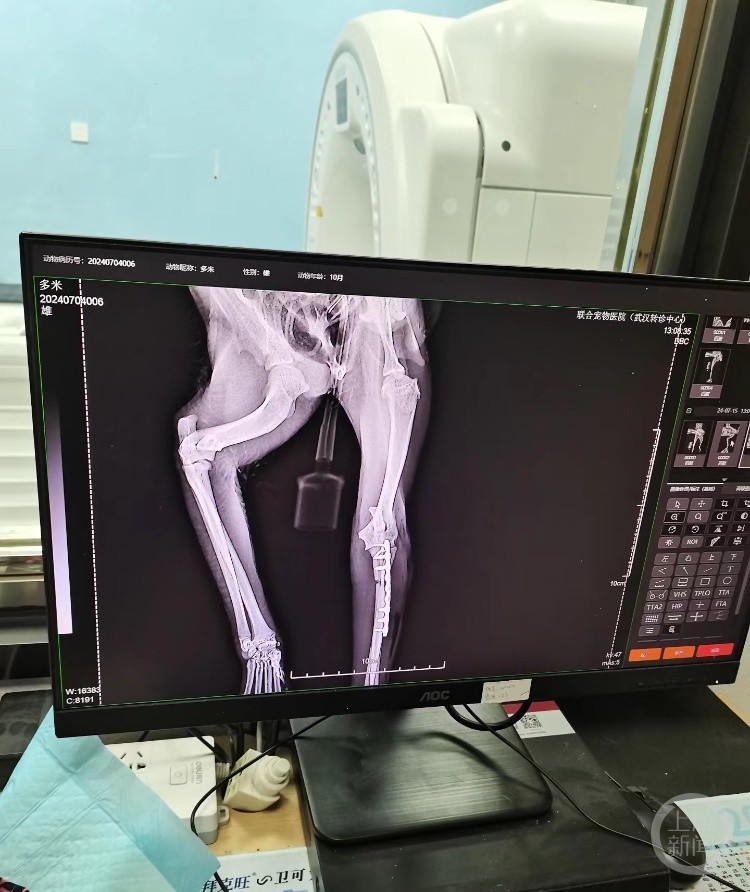

送医后经诊断,多米两条后腿都有伤,一条骨折一条韧带断裂,还伴随肺挫伤等多种症状,情况危急。但幸运的是,经两天抢救以及后续的骨折手术和长达半年的康复,在花掉近两万元医疗费后,多米恢复了健康。

蔡医生表示,此事确有其事。“多米是我从医7年以来,坠楼层数最高的一只猫咪。”蔡医生说,送医时多米的状态非常差,但不幸中的万幸,它的肺摔移位了但没有破。多米体重较轻,从楼上坠落的时间较长,它可能在空中调整过姿势。多米之前,另一只猫从6楼摔下,送来时肺破了,抢救无效去世。”